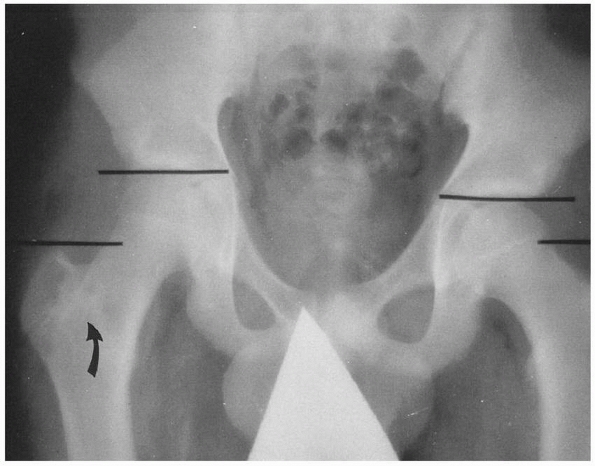

treated with intramedullary rodding, either as delayed or primary

treatment, including those caused by gunshot wounds and high-velocity

injuries.15,198

Antegrade intramedullary rod insertion maintains length, prevents

angular malunion and nonunion, and allows the patient to be rapidly

mobilized and discharged from the hospital. However, other techniques

with fewer potential risks should be considered.

In a large patient approaching skeletal maturity (bone age >16

years) but with an open proximal femoral physis and an unstable

fracture pattern, this treatment might be considered as a way to avoid

the risk of osteonecrosis yet stabilize the fracture (Fig. 22-22).

If growth from the distal femur is predicted to be less than 1 cm, leg

length inequality should not be a problem. Ricci et al.172

have shown that the complication rate with this technique compares

favorably to that of antegrade nailing, with a higher rate of knee pain

but a lower rate of hip pain. The malunion rate was slightly lower with

retrograde rodding than with antegrade rodding of the femur.

decubitus position on a fracture table. The upper end of the femur is

approached through a 3-cm longitudinal incision proximal that allows

access to the lateral trochanteric entry point. The skin incision can

be precisely placed after localization on both the AP and lateral

views. Dissection should be limited to the lateral aspect of the

greater trochanter, avoiding the piriformis fossa. This prevents

dissection near the origin of the lateral ascending cervical artery

medial to the piriformis fossa. The rod should be inserted through the

lateral aspect of the greater trochanter. In children and adolescents,

it is preferable to choose the smallest implant with the smallest

diameter reaming to avoid damage to the proximal femoral insertion area.

according to the specifics of the implant chosen. In general, the

smallest rod that maintains contact with the femoral cortices is used

(generally 9 mm or less) and is locked proximally and distally (Fig. 22-23). Only one distal locking screw is necessary, but two can be used.112

Rods that have an expanded proximal cross-section should be avoided,

because they require excessive removal of bone from the child’s

proximal femur. The proximal end of the nail should be left slightly

long (up to 1 cm) to make later removal easier. The rod chosen should

be angled proximally and specifically designed for transtrochanteric

insertion (Fig. 22-24).

without extending to the capsule or midportion of the femoral neck.

Some systems provide a small diameter, semiflexible tube that can be

inserted up to the fracture site after initial entry-site reaming. This